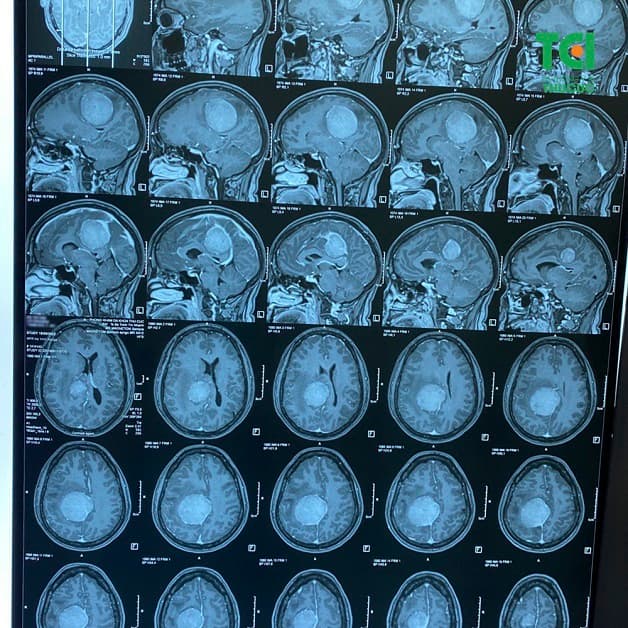

Như vậy ngoài biểu hiện u não gây mất ngủ thì còn có thể gây ra một loạt các triệu chứng khác. Nếu có dấu hiệu nghi ngờ đặc biệt là với những người thường xuyên đau đầu nên đi kiểm tra với bác sĩ chuyên khoa Nội thần kinh để được chụp cộng hưởng từ hoặc CT não, tầm soát và phát hiện sớm khối u não, từ đó xây dựng phác đồ điều trị (nội khoa hoặc phẫu thuật) hiệu quả.